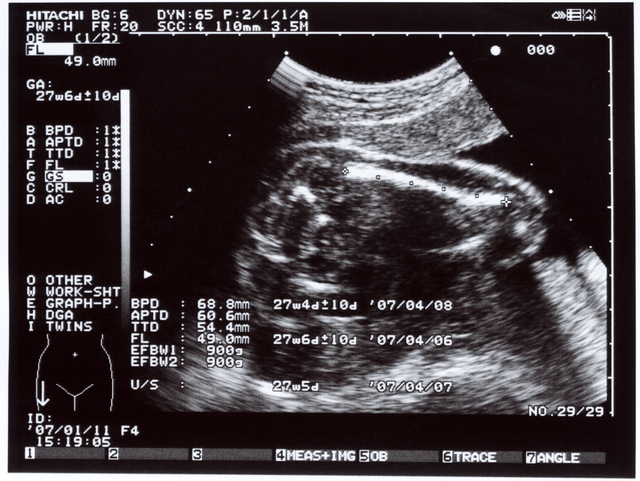

BPDはなに?

BPDは児頭大横径(じとうだいおうけい)、すなわち赤ちゃんの頭の大きさをあらわす数値です。Biparietal(両頭骨頂の) Diameter(直径)の略号となっています。

赤ちゃんの頭を真上から見て、左右の長さと前後の長さを直角に結んだ線の、左右の長さのことです。片方の頭蓋骨の内側からもう片方の頭蓋骨の外側までを結ぶことになっています。

FLはなに?

FLは大腿骨長(だいたいこっちょう)をあらわす記号で、Femur(大腿骨) Length(長さ)の略となっています。

大腿骨は太ももの付け根からひざまでの骨のことです。人間の骨の中で一番長い骨と言われ、胎児の発育具合を見る目安とされています。

APTD はなに?

APTDは腹部前後径(ふくぶぜんごけい)をあらわす記号で、Anterior-Posterior(前後) Trunk(胴) Diameter(直径)の略号です。

赤ちゃんの胴体の前後を測った数値になります。

TTD はなに?

TTDは腹部横径(ふくぶおうけい)をあらわす記号で、Transverse(横の) Trunk(胴体) Diameter(直径)の略になります。

赤ちゃんの胴体の左右の長さを測ったものになります。

EFWはなに?

EFWは胎児の推定体重をあらわす記号で、Eestimated(推定) Fetal(胎児の) Weight(重さ)の略となっています。

この値はBPD、AC、FLを使った数式を当てはめて、算出することになっています。